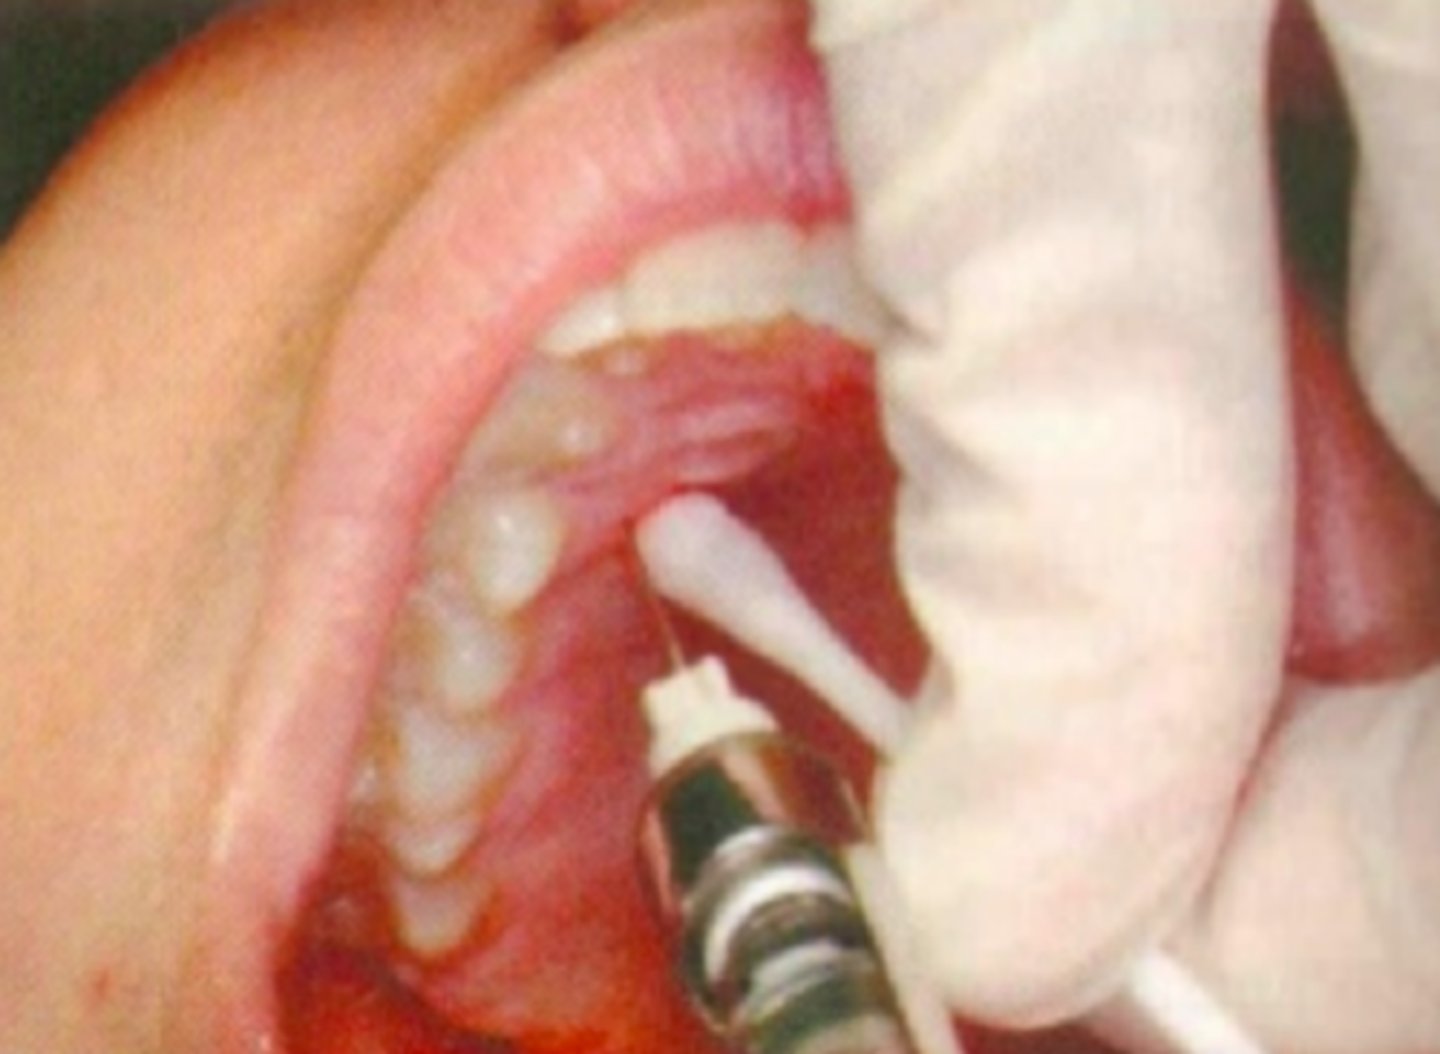

Palatogingival pain control for limited area (1-2 teeth) Achieving hemostasis during surgical procedure

What are the indications for a Palatal local infiltration?

-Infection/inflammation at injection site

-larger area of therapy (> 1 or 2 teeth)

What are some contraindications for a Palatal local infiltration?

Palatal Local Infiltration

ID the anesthesia technique:

10 or 11 o'clock

what is the operators position for a Palatal Local Infiltration:

27 short gauge

what size needle should you use for a Palatal Local Infiltration?

Palatal gingival tissue 5-10 mm from the free gingival margin

what is the needle target for a Palatal Local Infiltration?

Attached gingiva 5-10 mm from the free gingival margin

what is the insertion point for a Palatal Local Infiltration?

Approaching the injection site at 45 degree angle

what is the insertion path for a Palatal Local Infiltration?

3 to 5 mm

what is the insertion depth for a Palatal Local Infiltration?

0.2 to 0.3 ml

what is the anesthetic volume for a Palatal Local Infiltration?

This type of nerve block will result in the anesthesia of the palatal soft tissue in the immediate adjacent area of injection?